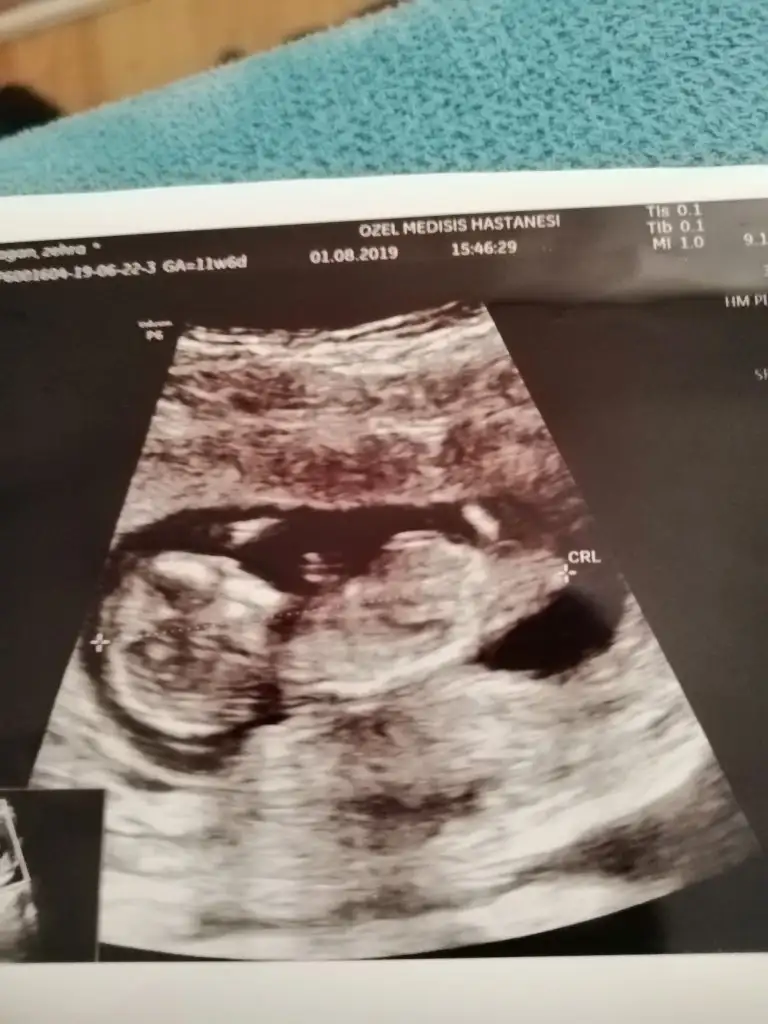

Bunlarda az önce alınan resimler normalde 11 hafta 6 günlük ama usg de 12 hafta 6 günlük

Siz erkek istiyordunuz galiba.nub çizgisine ve kafa yapısına göre yorum yapıyorum.cinsiyet oluşmadan önce nub çizgisi oluşur.bu çizgi paralelse kız,dik ise erkek demektir.sizin bebeğinizin nub çizgisi bariz paralel.kafa yapısı da oval.erkeklerin kafa yapısı daha yuvarlak olur. Doktor kesin erkek dedi mi size? Buda cinsel organı diye gösterdi mi? Kaç haftalıksınız şuan?Doktor organını bile gösterdi bu çıkıntı olabilir diye yine de cevabınız için teşekkür ederim merakımdan soruyorum yanlış anlamayın neye göre Tahminde bulunuyorsunuz mesela son resim tam olarak neyi gösteriyor hiçbirşey anlamadım

Evet gönlümden geçen erkek Bi tane kızım var çok ta sevinmiştim siz şimdi kesin kız deyince moralim bozuldu biraz. Şu an sat a göre 11 hafta 6 gün usg ye göre 12 hafta 6 gün. Doktor erkeğe çok benziyor çıkıntısı burada diyerek gösterdi kesin erkek demedi yüzde 80 erkek dedi ama bazen kızlarda da bu çıkıntı oluyor dedi. Hatta bu Nub teorisinden de bahsettim belli olmaz bazen dik bazen paralel bile olabilir dediSiz erkek istiyordunuz galiba.nub çizgisine ve kafa yapısına göre yorum yapıyorum.cinsiyet oluşmadan önce nub çizgisi oluşur.bu çizgi paralelse kız,dik ise erkek demektir.sizin bebeğinizin nub çizgisi bariz paralel.kafa yapısı da oval.erkeklerin kafa yapısı daha yuvarlak olur. Doktor kesin erkek dedi mi size? Buda cinsel organı diye gösterdi mi? Kaç haftalıksınız şuan?

Erkek gibi.duruş pozisyonu dik olunca kız mı erkek mi karar veremedim açıkçası.ama oyumu erkekten yana kullanıyorum. Kız da olabilir ama.ay emin olamadım bu usg deyok yok kız bu

Kızlarda da bu çıkıntı oluyor dediyse nub çizgisinden bahsediyor.11 12 haftada cinsel organ tam anlamıyla oluşmuyor nub çizgisi oluyor.13 14 haftalarda organ oluşmuş oluyor.yani direkt olarak pipi göstermemiş.bilmiyorum doktor erkek dediyse erkek olabilir.ben bariz kız görüyorum bu usg de.elbette doktorlar daha iyi bilir tabi.rabbim gönlünüzdekileri nasip etsin inşallah.siz sorduğunuz için cevapladım.ama bana göre bu bebiş kızEvet gönlümden geçen erkek Bi tane kızım var çok ta sevinmiştim siz şimdi kesin kız deyince moralim bozuldu biraz. Şu an sat a göre 11 hafta 6 gün usg ye göre 12 hafta 6 gün. Doktor erkeğe çok benziyor çıkıntısı burada diyerek gösterdi kesin erkek demedi yüzde 80 erkek dedi ama bazen kızlarda da bu çıkıntı oluyor dedi. Hatta bu Nub teorisinden de bahsettim belli olmaz bazen dik bazen paralel bile olabilir dedi